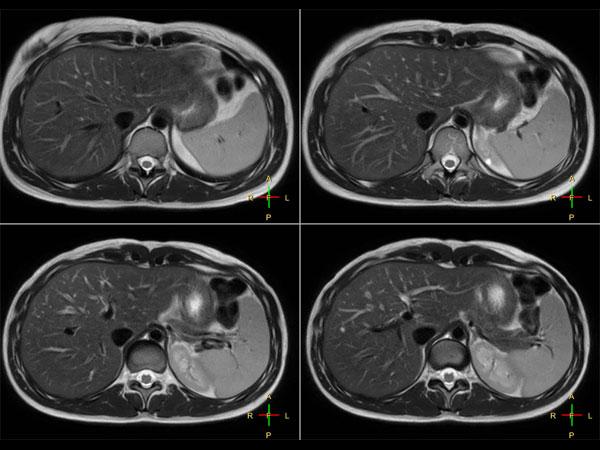

Liver imaging with MultiVane XD